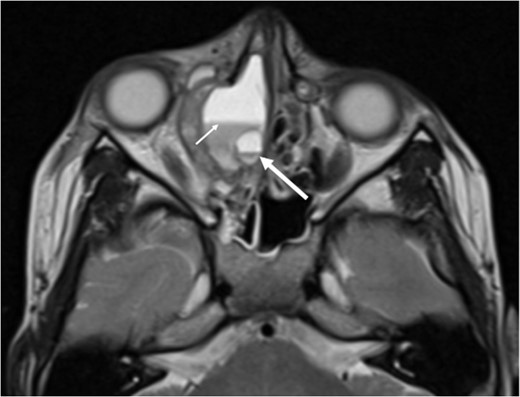

A 6-year-old boy with a background of asthma presented to a tertiary paediatric unit in May 2016 with a 3-day history of right eye pain, proptosis and erythema under the care of the ENT team. A provisional diagnosis of a periorbital cellulitis was made secondary to ethmoid sinusitis and management with intravenous antibiotics (ceftriaxone), intranasal steroids, saline douches and topical oxyxlometazoline was initiated. Ophthalmological assessment demonstrated normal colour vision, acuity and light reflexes bilaterally but also proptosis-related ophthalmoplegia. Computed tomography (CT) imaging of the orbits and paranasal sinuses demonstrated complete opacification of the right-sided paranasal sinuses and compromise of the right frontal and ostiomeatal unit. In addition there was an expansile abnormality centred on the ethmoidal labyrinth with bony remodelling of the lamina papyracea and a subperiosteal collection adjacent to the medial orbital wall (Figs 1 and 2). The most likely diagnosis was felt to be an infective process with mucopyocele formation complicated by a subperisoteal post-septal collection. An MRI scan with gadolinium of the orbits and sinuses confirmed the unilateral pattern of sinus opacification within the right frontal, ethmoids and maxillary sinus. The lesion demonstrated multiple fluid–fluid levels and peripheral enhancement (Figs 3 and 4). The patient was treated by endoscopic drainage of the lesion, which revealed only blood. He initially had some improvement of his proptosis but recurred within a few days and so further, more extensive endoscopic debridement was performed.

Axial T2 weighted sequence demonstrating the presence of multiple fluid filled levels (short white arrow) within the expansile lesion and smaller cyst present within the larger cyst (long white arrow).

At this point the MRI was reviewed and the possibility of an ABC was raised. This was due to the presence of fluid–fluid levels, cyst within a cyst appearance and lack of restricted diffusion within the sinonasal contents and material drained at the time of the first endoscopic procedure. He was discharged home on oral co-amoxiclav, and topical betamethasone nose drops.